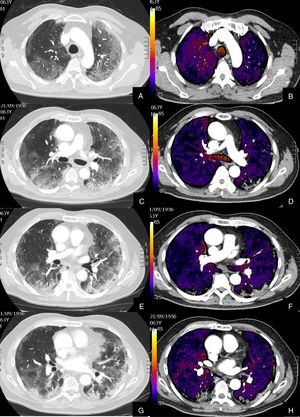

Paciente con COVID-19 que después de una semana de ingreso hospitalario persiste con desaturación que no corrige con flujo elevado de O2.

Imágenes axiales de la angiografía pulmonar con TC y mapa de yodo en ventana de parénquima (A, C, E, G) desde el cayado aórtico hasta los lóbulos inferiores y su correlación con el mapa de yodo (B, D, F, H).

Parénquima con afectación severa en vidrio deslustrado de predominio subpleural y segmentos posteriores de todo el pulmón, sin TEP visible. El mapa de yodo muestra una severa hipoperfusión difusa de todo el pulmón tanto afectado como sano (zonas azules y negras) en probable relación con microtrombosis difusa del lecho capilar.